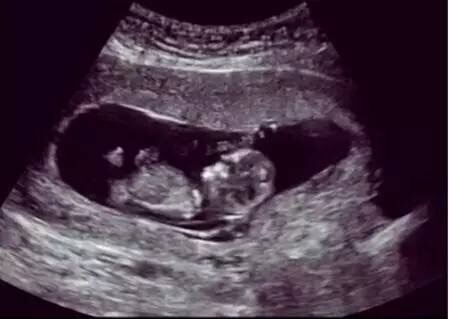

那超聲波對胎兒有害嗎?

超聲波使用的是一種聲波,不是離子射線。目前為止,從沒有過診斷性超聲波造成胎兒損傷的報道出現(xiàn),包括多普勒彩超。孕期超聲波是不受威脅的,這也是為什么現(xiàn)代婦產(chǎn)科產(chǎn)檢不用x線,而常規(guī)用超聲波。